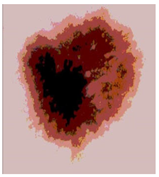

![]() | ![]() | ![]() | ![]() |

| Img1 | --- Pixel Intensity (0–255) ---> | ||

| Img2 | --- Pixel Intensity (0–255) ---> | ||

| Img3 | --- Pixel Intensity (0–255) ---> | ||

| Img4 | --- Pixel Intensity (0–255) ---> | ||

| Img5 | --- Pixel Intensity (0–255) ---> | ||

| Img6 | --- Pixel Intensity (0–255) ---> | ||

| Img7 | --- Pixel Intensity (0–255) ---> | ||

| Img8 | --- Pixel Intensity (0–255) ---> | ||

| Img9 | --- Pixel Intensity (0–255) ---> | ||

| Img10 | --- Pixel Intensity (0–255) ---> | ||